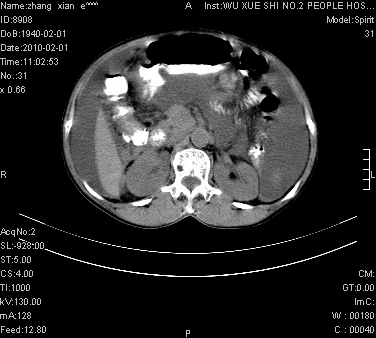

标题: CT24434:70岁 女 腹胀,腹水原因待查 [打印本页]

标题: CT24434:70岁 女 腹胀,腹水原因待查

腹盆腔大量积液,子宫增大,子宫颈增大外形不规则,内见低密度影,膀胱后壁显示不清,右腹股沟肿大淋巴结,脾脏囊性占位,子宫颈占位,子宫颈癌?建议增强。

考虑:1、腹膜转移,大量腹水;

2、脾占位性病变;

3、左侧卵巢占位性病变,建议增强进一步检查。

大量腹水,右肾、脾囊肿可能性大          考虑左侧附件区占位,建议增强

考虑:1、腹膜转移,大量腹水;2、脾占位性病变;3、左侧卵巢占位性病变,建议增强进一步检查。支持